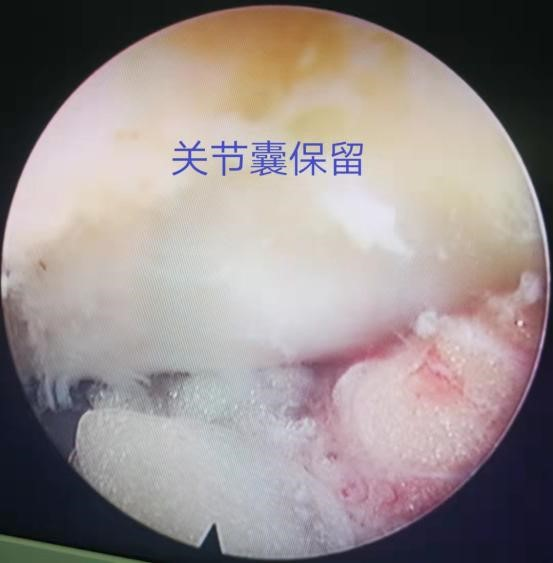

为解决以上问题���,我们提出“椎间孔镜按需成型5级法”��,即将椎间孔镜术中椎间孔成型的实际操作范围进行分级���:0级����:不成型����,见图 1��;1级���:软组织成型�����,只去除关节囊等部分软组织�����,基本不做骨性成型���,见图 2���;2级�����:少许骨质成型���,但不显露下关节突关节面����,见图 3����。3级成型�����:上关节突尖部或上1/2去除成型���,显露下关节突关节面���,见图 4�����;4级成型����:上关节突大部分成型或伴有部分椎弓����、峡部或下关节突小部分���,但预留基底部一部分��,见图 5��。

图 2 1级成型 |